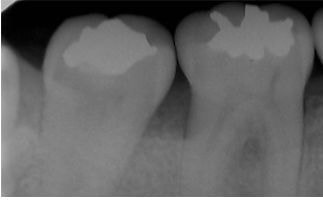

問診・視診・打診・温度診・レントゲンなどの検査を行っても原因が特定できない場合でも、マイクロスコープで検査を行うことで何が原因になっているか特定できる症例はたくさんあります。